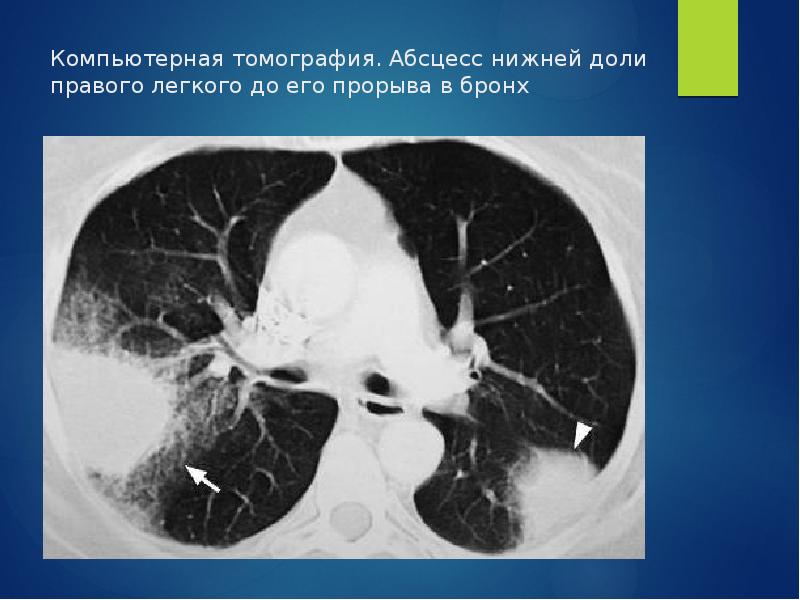

Фотографии и снимки КТ легких без контрастных веществ

Раздел: Визуальный дайджест